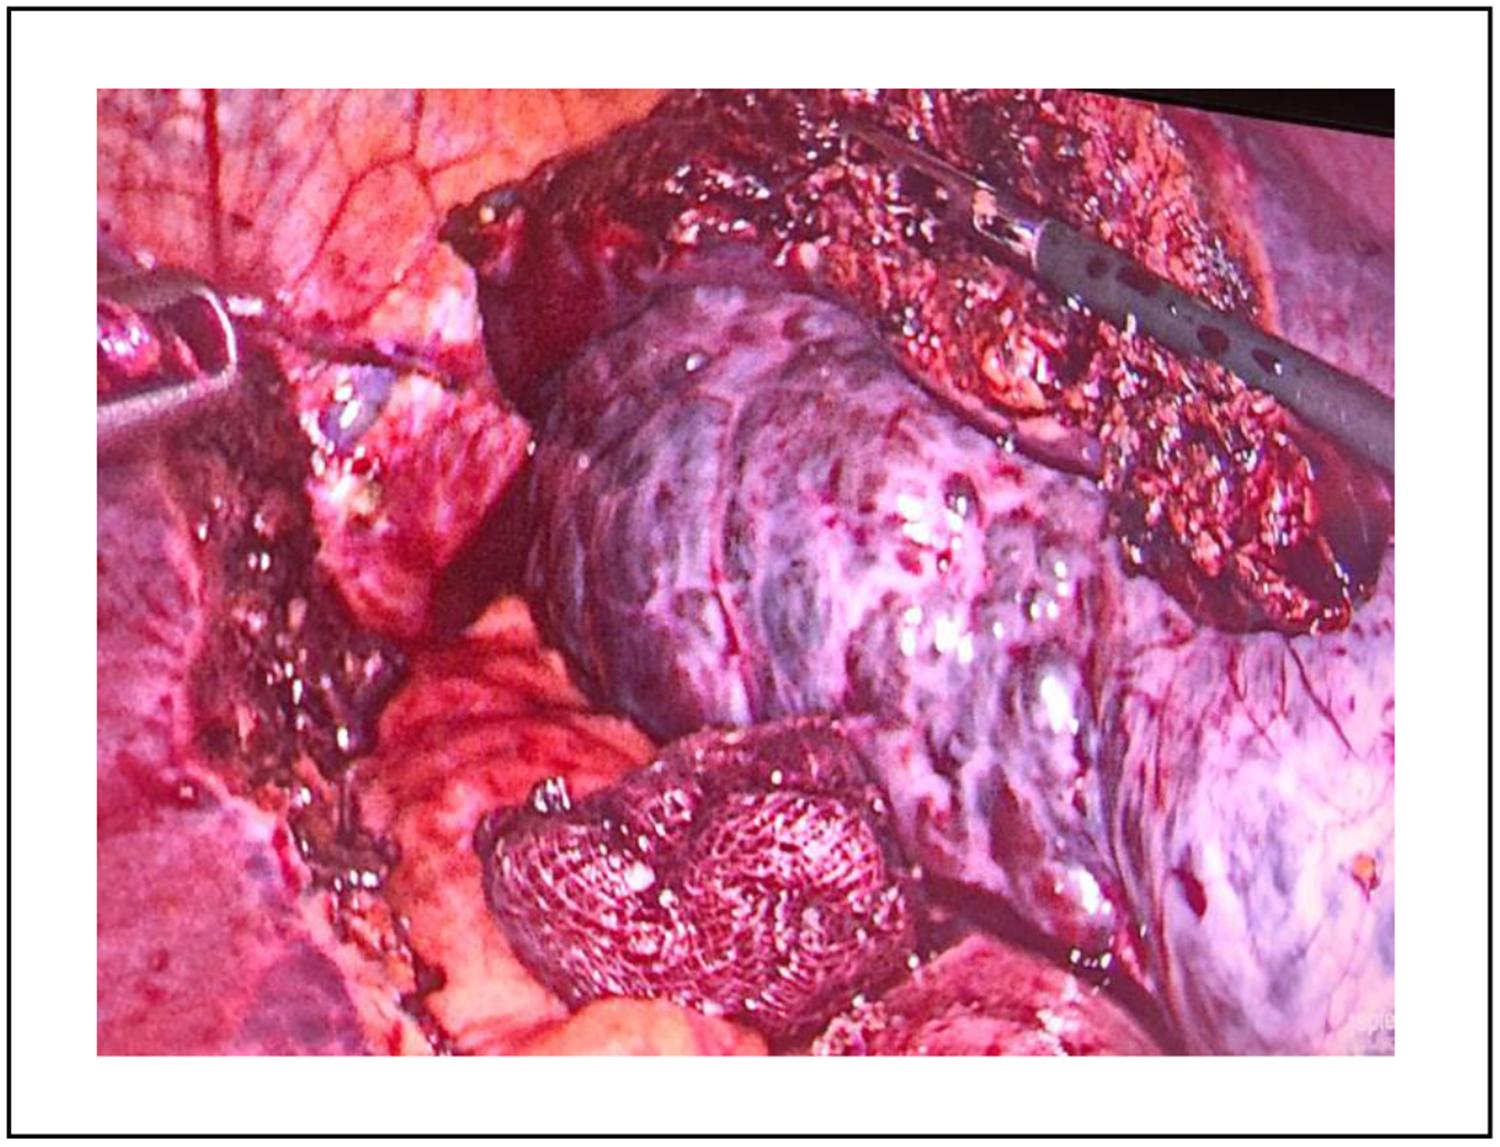

Una vez realizados los estudios se lleva a cabo la hepatectomía laparoscópica. Esta intervención requiere al paciente en posición francesa y la colocación de 4 trocares, como se muestra en la Figura 3. A partir de esto es posible explorar la cavidad e identificar un hemangioma hepático emergente. Se logró el control del pedículo vascular mediante la colocación de un lazo vascular, sin necesidad de clampeo hepático, dado que no se presentó un sangrado significativo. Posteriormente, fue posible una transección hepática con Sonicision®; se sellaron los pedículos segmentarios II y III y la vena suprahepática izquierda, mediante endograpadora vascular (dorada, 2 mm, tres líneas de grapas). Se deja drenaje de Blake enfrentado a tranche, sacado por contrabertura. Finalmente, la pieza fue retirada (Figura 4 y 5) a través de una incisión mediana supraumbilical, protegida con separador de Alexis.

Figura 4. Cirugía laparoscópica, hepatectomía atípica. La fleche señala pieza de resección.La pieza quirúrgica se envió para análisis anatomopatológico, el cual confirmó el diagnóstico de hemangioma cavernoso. (Figura 5).